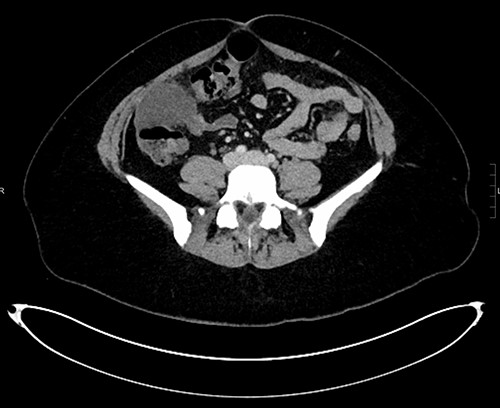

The white cell count was 10.5 × 109/l, C-reactive protein 6.8 mg/l, B-hCG negative, urine culture negative. Ultrasound (US) abdomen did not identify the appendix or the right ovary but noted a 102 × 43 × 52 mm complex multi-locular cyst. Computed tomography (CT) abdomen showed a focal low-density mass with adjacent inflammatory change anterior to the ascending colon measuring 43 × 55 × 54 mm (Figs 1–3). This mass appeared separate to the ovary and the appendix.

Axial CT demonstrating mass anterior to ascending colon with surrounding inflammatory changes.